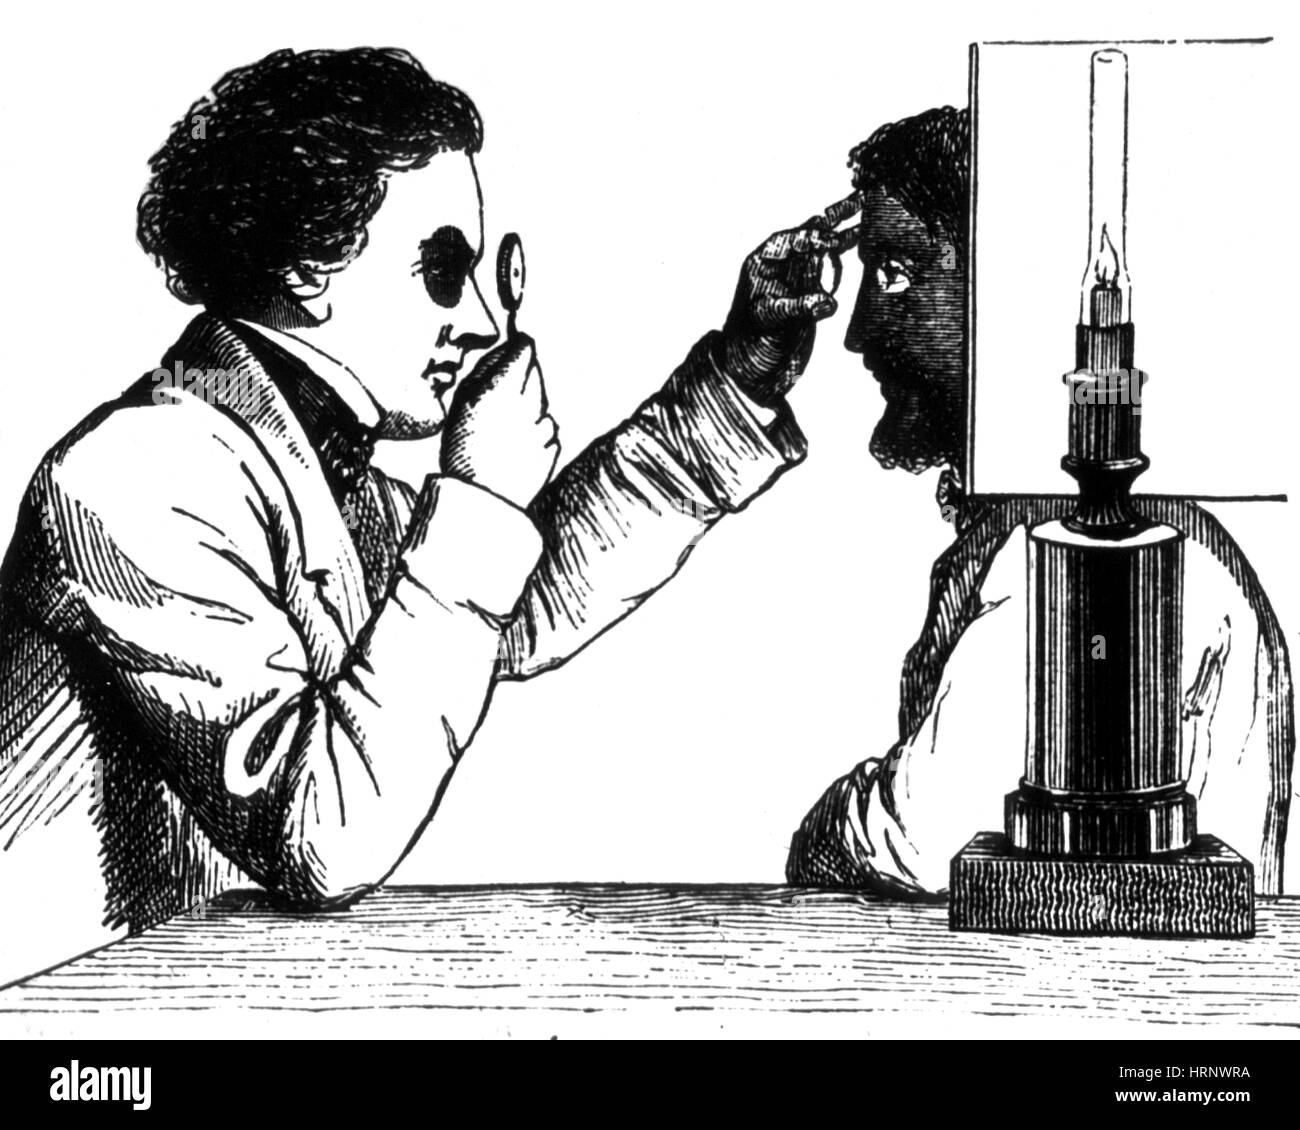

Engraving depicting an ophthalmoscope in use. Ophthalmoscopy, also called funduscopy, is a test that allows a health professional to see inside the fundus of the eye and other structures. The ophthalmoscope was invented by Hermann von Helmholtz (1821-1894) a German physician and physicist. Dated 19th century Stock Photohttps://www.alamy.com/image-license-details/?v=1https://www.alamy.com/engraving-depicting-an-ophthalmoscope-in-use-ophthalmoscopy-also-called-funduscopy-is-a-test-that-allows-a-health-professional-to-see-inside-the-fundus-of-the-eye-and-other-structures-the-ophthalmoscope-was-invented-by-hermann-von-helmholtz-1821-1894-a-german-physician-and-physicist-dated-19th-century-image186347727.html

Engraving depicting an ophthalmoscope in use. Ophthalmoscopy, also called funduscopy, is a test that allows a health professional to see inside the fundus of the eye and other structures. The ophthalmoscope was invented by Hermann von Helmholtz (1821-1894) a German physician and physicist. Dated 19th century Stock Photohttps://www.alamy.com/image-license-details/?v=1https://www.alamy.com/engraving-depicting-an-ophthalmoscope-in-use-ophthalmoscopy-also-called-funduscopy-is-a-test-that-allows-a-health-professional-to-see-inside-the-fundus-of-the-eye-and-other-structures-the-ophthalmoscope-was-invented-by-hermann-von-helmholtz-1821-1894-a-german-physician-and-physicist-dated-19th-century-image186347727.htmlRMMR4TBY–Engraving depicting an ophthalmoscope in use. Ophthalmoscopy, also called funduscopy, is a test that allows a health professional to see inside the fundus of the eye and other structures. The ophthalmoscope was invented by Hermann von Helmholtz (1821-1894) a German physician and physicist. Dated 19th century

Early Ophthalmoscope, 1873 Stock Photohttps://www.alamy.com/image-license-details/?v=1https://www.alamy.com/stock-photo-early-ophthalmoscope-1873-135090910.html

Early Ophthalmoscope, 1873 Stock Photohttps://www.alamy.com/image-license-details/?v=1https://www.alamy.com/stock-photo-early-ophthalmoscope-1873-135090910.htmlRMHRNWRA–Early Ophthalmoscope, 1873